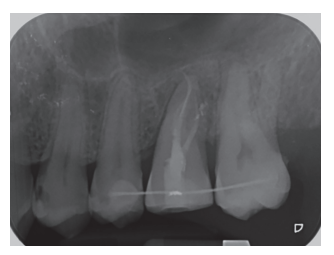

En la exploración radiográfica, mediante radiografía panorámica, se apreciaron ambos terceros molares inferiores retenidos, en posición horizontal (Figura 3), e imágenes radiolúcidas apicales en posición de 2.6 y 4.6. En el escáner de haz cónico se evaluó la morfología radicular del tercer molar superior izquierdo, y la dimensión de la lesión radiolúcida apical del primer molar superior izquierdo (Figura 4), datos necesarios para valorar el grado de adaptación del diente donante en el lecho receptor.

Tras rebajar la oclusión, se dio un punto en cruz con sutura monofilamento (Aragó®, Barcelona, España) alrededor del diente trasplantado para aumentar su fijación (Figura 13), realizándose una radiografía periapical intraoperatoria con técnica de paralelismo (Figura 14).

Transcurridos 2 meses se realizó una nueva revisión clínica (Figura 17) y radiográfica mediante radiografía periapical (Figura 18), procediéndose a retirar la ferulización. A los 3 meses se realizó otra revisión clínica (Figura 19) y radiográfica mediante radiografía periapical paralelizada (Figura 20), donde se puede observar una adecuada formación ósea alrededor del diente trasplantado.